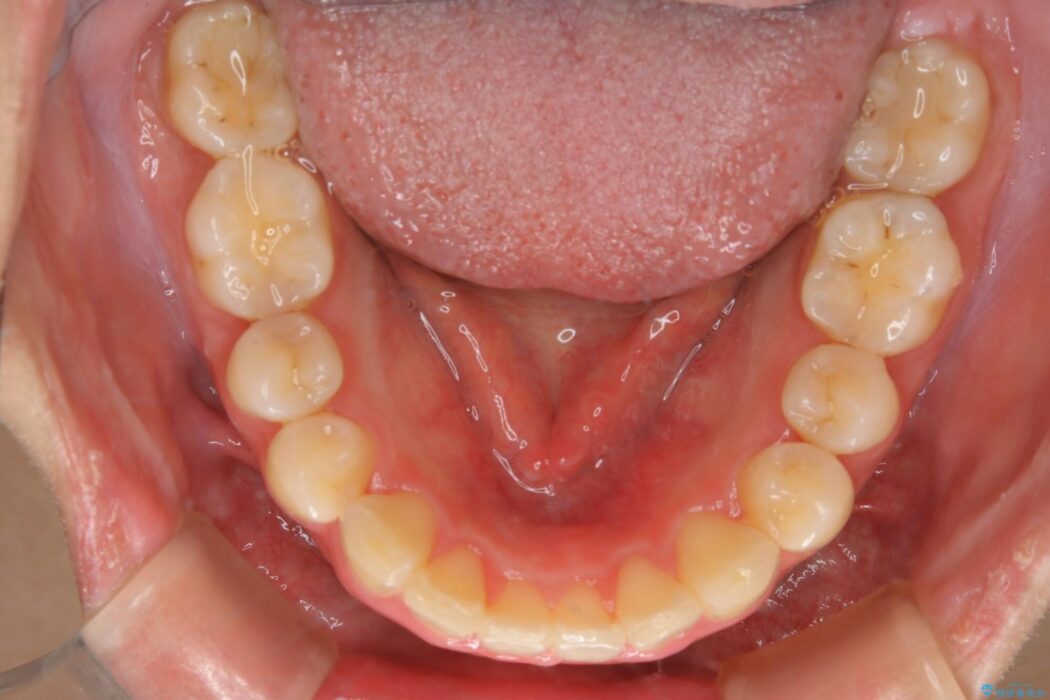

治療後について

口元が後方に下がったことにより横から見たEラインが改善し、口元の印象が変わったと患者様にとても喜んでいただけました。